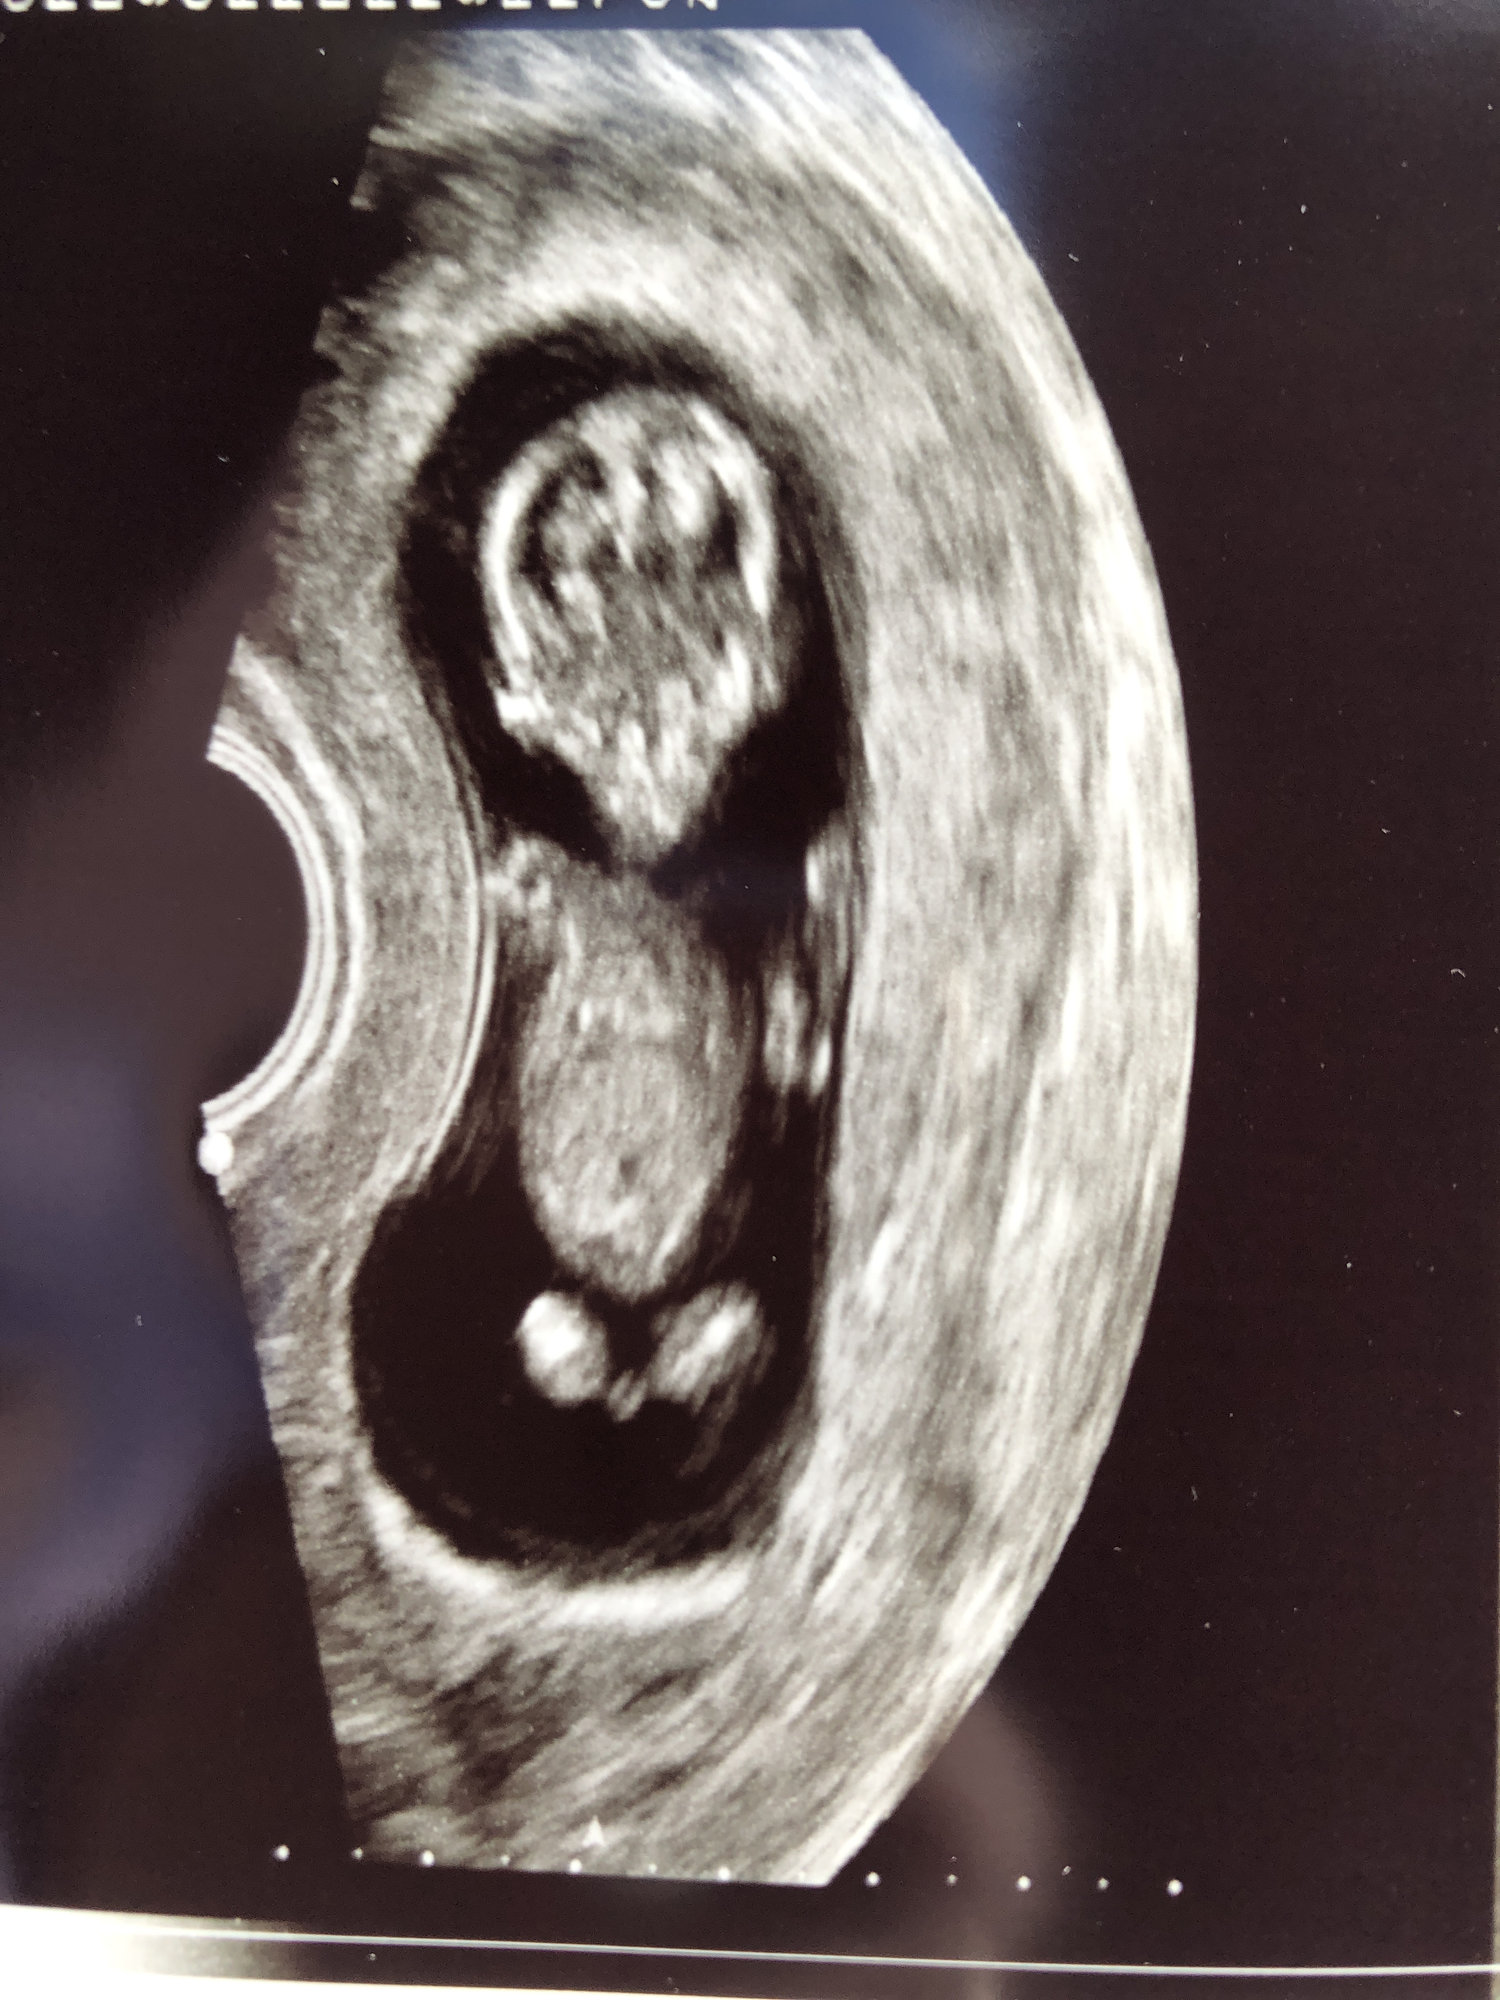

My ultrasound at 13 weeks when I went in for the NT scan! Had no idea that there are two in there !